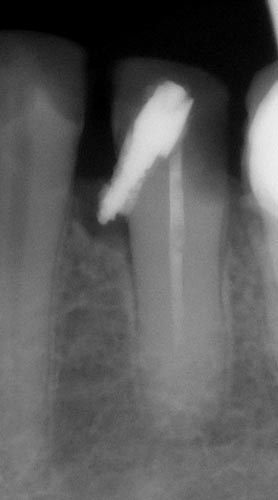

Перфорації кореневого каналу

• клініка

• діагностика

• менеджмент

Перфорації корня каналу

Класифікація перфорацій. Вплив розташування на прогноз і тактику.

Вибір матеріалу в залежності від розташування і розміру перфорації( фуркаційна, середньої третини і апікальна)

Чи є найкращий матеріал для закриття перфорації?

Правила використання композиту для закриття перфорації.

Використання біокерамічних силерів, переваги і недоліки

Сучасний «золотий стандарт» МТА? Чому МТА може не застигати? Робота з перфорацією один чи два візити? Вплив на прогноз. Відеодемонстрація роботи з різними матеріалами і різною локацією. Допоміжне обладнання при роботі з мікроскопом і без. Прогноз закриття перфорацій. Розгляд клінічних питань слухачів щодо перфорацій( підготувати клінічні ситуації). Вебінар надає 1 бал БПР,